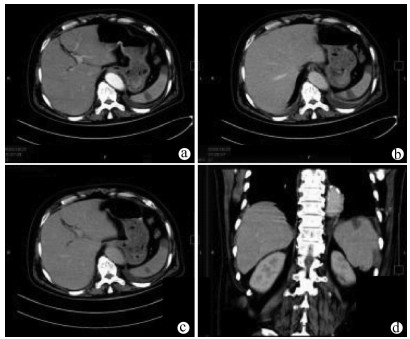

Primary biliary cholangitis with hepatic angiosarcoma: A case report

Jiamin ZHAO, Zhiyuan CHEN, Chengliang DING, Lili YUAN, Jingjing QIAN, Chunyang XU, Lingyun ZUO

2021, 37(10): 2411-2413. DOI: 10.3969/j.issn.1001-5256.2021.10.031

Abstract(780) HTML (186) PDF (2456KB)(66)

Abstract: